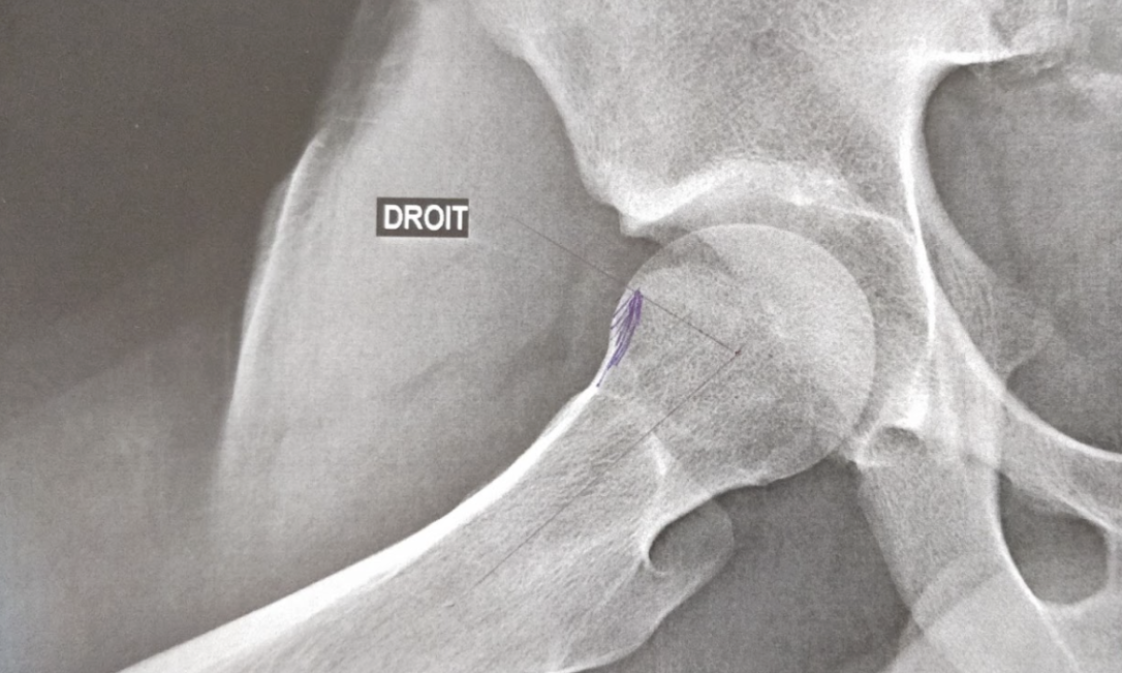

Le diagnostic du conflit fémoro-acétabulaire de la hanche est généralement établi par Dr Olivier Gastaud à l’aide d’examens d’imagerie tels que des radiographies, une IRM ou un arthroscanner de la hanche.